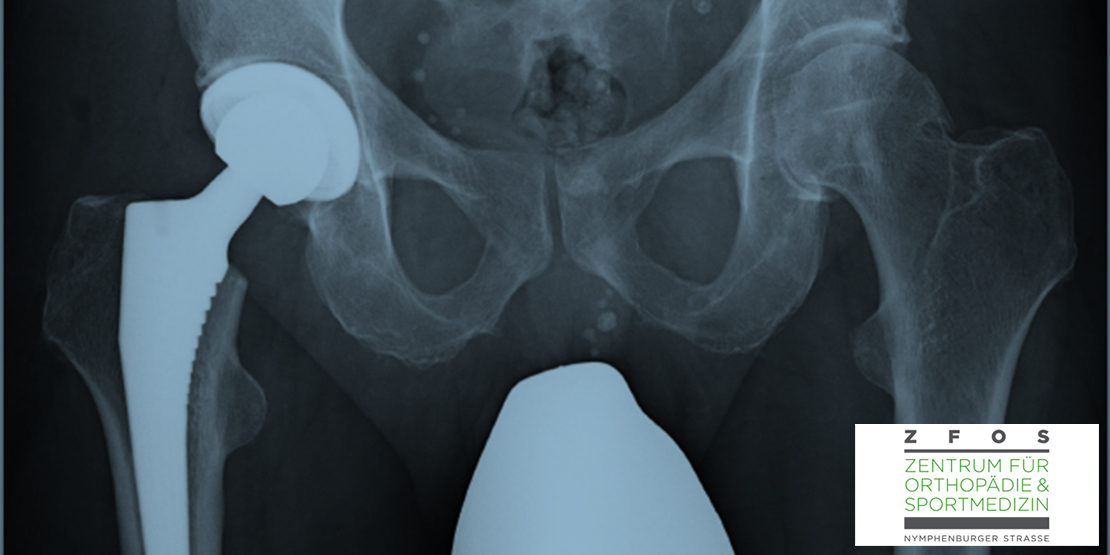

Die Arthrose von Knie- und Hüftgelenk ist eine in Deutschland sehr häufige degenerative Gelenkerkrankung, die im fortgeschrittenen Stadium eine schmerzfreie Mobilität und Aktivität sehr einschränken kann. Nach Ausschöpfen der nicht operativen Therapiemaßnahmen ist ein künstlicher Gelenkersatz häufig sinnvoll. Dr. Christoph Rummel, Spezialist für Endoprothetik beim ZFOS in München, informiert in diesem Gastbeitrag über Wissenswertes vor und nach der Operation.

Bevor die Operation stattfindet, sollte der Patient von einem spezialisierten und erfahrenen Operateur untersucht werden, um den Zustand des Gelenks zu beurteilen und die Notwendigkeit eines künstlichen Gelenks festzustellen. Es werden Röntgenaufnahmen und möglicherweise andere bildgebende Untersuchungen durchgeführt. Darüber hinaus werden die medizinische Vorgeschichte und der Gesundheitszustand des Patienten bewertet. Die Planung umfasst auch die Auswahl der passenden Implantate für den individuellen Fall.